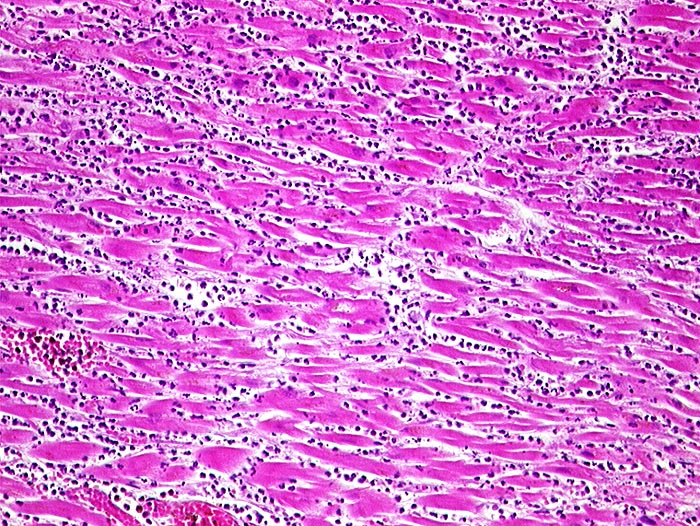

PathoPic – image database / PathoPic ID 816 - Akuter Myokardinfarkt

Akuter Myokardinfarkt

Nekrotische Myokardfasern ohne erkennbare Kerne. Dichtes granulozytäres Infiltrat.

Paninfarkt bei schwer stenosierender Koronarsklerose mit Abgangstenose beider Hauptäste. Alter Verschluss der Arteria coronaria dextra.

Zelluläre Infiltrate sind nach minimal 3 Stunden sichtbar. Kontraktionsbänder entstehen, wenn das hypoxisch geschädigte Myokard sich noch kontrahiert, aber nicht mehr relaxieren kann.